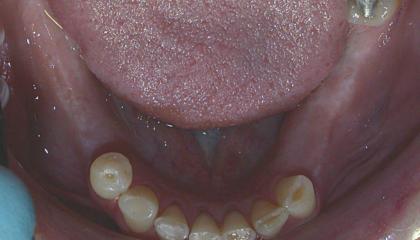

Before

Single Dental Implant